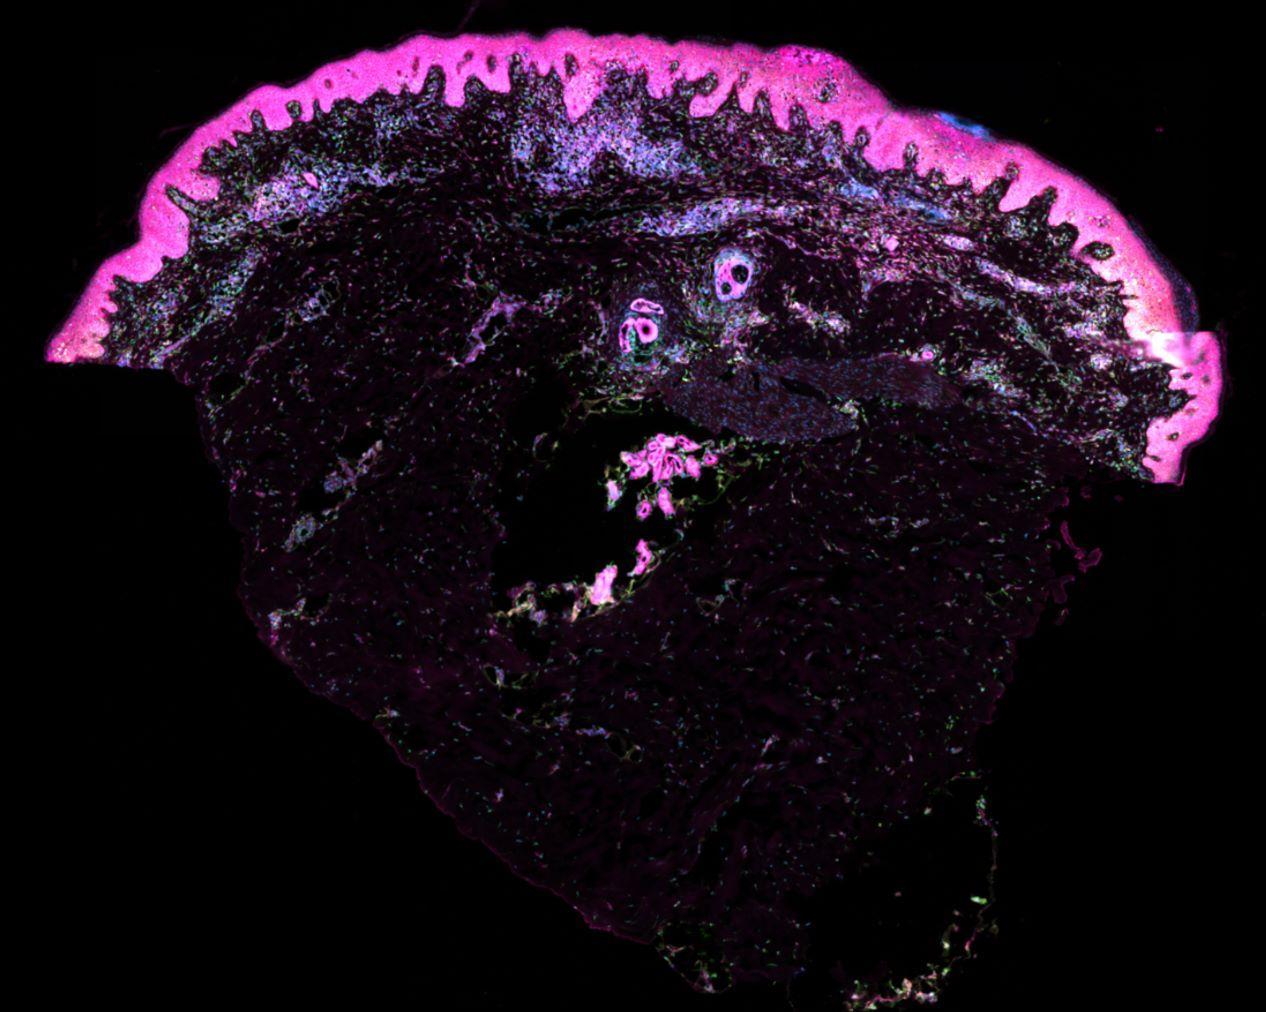

在实验中,研究团队在培养皿创建了一个能够生长毛发的“迷你皮肤器官”。利用这一类器官,他们发现了免疫细胞在无瘢痕皮肤修复中的重要作用。

研究团队使用了产前胚胎皮肤组织样本,将其分解以观察悬浮状态的单个细胞以及组织内细胞。他们利用单细胞测序和空间转录组学技术,分析了时间和空间中的单个细胞变化,以及调节皮肤和毛囊发育的细胞机制。他们描述了人类毛囊形成的步骤,并确定了其与小鼠毛囊的差异。

团队发现,在利用成体干细胞创建的“迷你皮肤器官”中,血管形成不如胚胎皮肤完善。通过将巨噬细胞添加到此类器官中,他们发现巨噬细胞能促进血管形成,并进行了3D成像以评估组织内的血管形成情况。